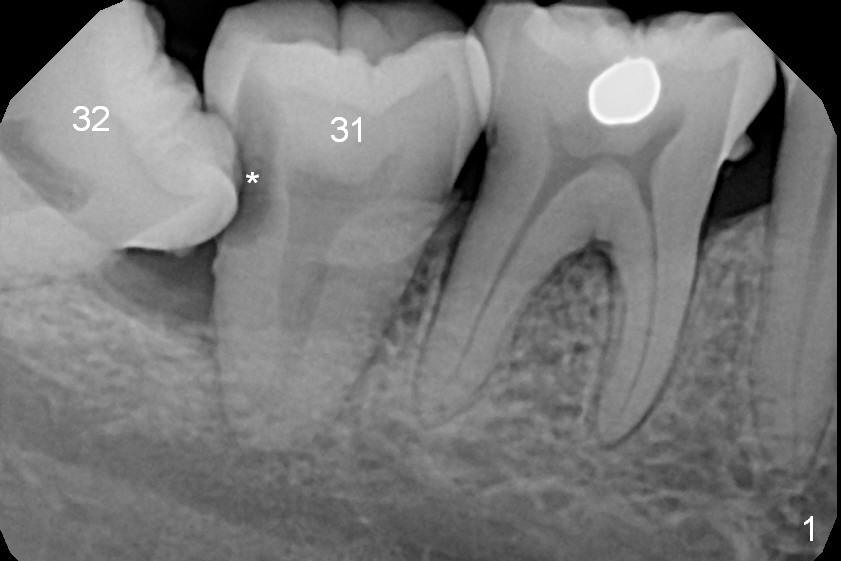

A 39-year-old woman has pain and mobility associated with the tooth #31 (Fig.1 (taken 5 months earlier), 2). It is easy to extract the mesioangularly impacted third molar (#32) after extraction of #31. After debridement and Clindamycin socket disinfection, collagen plug is placed in #32 socket, while allograft in the bottom half of the #31 one. The most coronal portion of the sockets are packed with mixture of collagen and Osteogen plugs and fixed in place with 4-0 Chromic gut (Fig.3). Two or 3 months postop, use #15 to start bone expansion at #31, followed by osteotomes or bone expanders and Tatum tapered taps. Take preop X-ray for depth measurement. The socket is close to the Inferior Alveolar Canal. In one word, no drill will be used for osteotomy. Place bone graft (Fig.4 red circles) prior to implant placement (white outline). Take CT post implant placement to confirm that the Inferior Alveolar Nerve is lingual to the implant.